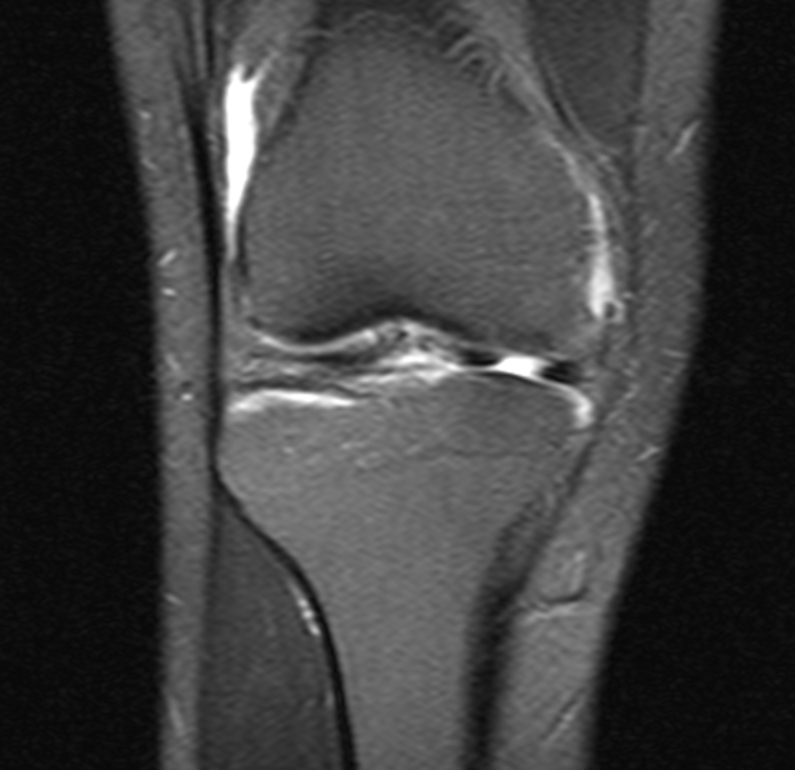

Menisküs Yırtığı: Belirtiler, Tanı ve Kişiye Özel Tedavi Yaklaşımı

Menisküs yırtığı; boşalma/kilitlenme hissi ve eforla artan ağrıya yol açar. Muayene ve MR ile yırtığın tipi belirlenir. Uygun hastada doku koruyucu artroskopik onarım, diğerlerinde parsiyel menisektomi ve yapılandırılmış rehabilitasyonla günlük yaşama ve spora güvenli dönüş hedeflenir.

Menisküs Yırtığı Belirtileri ve Tedavi Yöntemleri

Dizde kilitlenme, ağrı ve şişlik ile kendini gösteren menisküs yırtıklarının tanısı ve modern tedavi yaklaşımları.